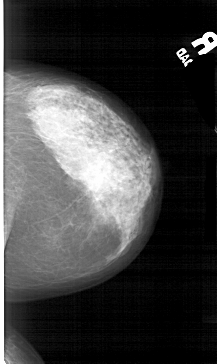

A_1544_1.RIGHT_MLO

RIGHT_MLO LINES 5491 PIXELS_PER_LINE 3076 BITS_PER_PIXEL 12 RESOLUTION 43.5 NON_OVERLAY